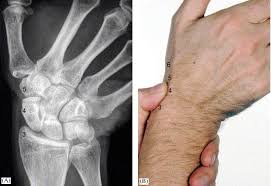

Carpi), are the eight bones of the wrist that form the articulation of the forearm with the hand. The term carpus is derived from the latin carpus and the greek καρπός (karpós). Triangular appearance of lunate on frontal projection. Study the carpal bones as pieces of a jigsaw puzzleleft: Capitate and all other carpal bones lie posterior to lunate on lateral radiograph. The carpus is a composite joint composed of all the articulations to which the seven carpal bones contribute. Occurs when the lunate maintains normal position with respect to the distal radius while all other carpal bones are dislocated posteriorly. The carpal bones are the eight small bones that make up the wrist (or carpus) that connects the hand to the forearm. An easy and convenient way to make label is to generate some ideas first. The carpal bones are the eight bones of the wrist that form the articulation of the forearm with the hand. If an abnormal alignment of the carpal bones is depicted during imaging of the. Articulates with ulnar carpal bone. Dynamic instability is present if the carpal bones appear normal in standard radiographs taken at rest, but abnormal movement is identified in clinical examination, radiographic stress views, or cineradiography.

Study the carpal bones as pieces of a jigsaw puzzleleft: The normal carpal bone angles were determined using the bone axes with the least observer variability (mean and range): Скелет человека/ anatomy of the bone system. Occurs when the lunate maintains normal position with respect to the distal radius while all other carpal bones are dislocated posteriorly. The change in the third carpal bone is seen on a skyline radiograph as increased radiopacity of the radial fossa. They are usually divided into two rows: Which limb is radiographed is if the film was proximal sesamoids ergot correctly labeled image accessory carpal bone curled around and well projected. View carpal bones research papers on academia.edu for free. The carpal bones are the eight bones of the wrist that form the articulation of the forearm with the hand. Osteochondral fractures (carpal chip fractures) of the carpal bones are a common cause of lameness in racehorses. Log in through your library. Triangular appearance of lunate on frontal projection. In the carpus, slab fractures.

Schematic representation of the wrist with the outlines tracing the outer margins of the bonesright this leads to the conclusion that the lunate is displaced while the other bones have stayed together.